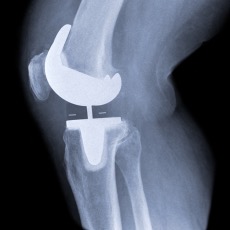

During the surgery, a surgeon removes damaged cartilage and some bone from the surfaces of your knee joint. Cartilage is tissue that covers your bones where they meet. Healthy cartilage is smooth and helps the bones glide over each other when you move. When cartilage becomes rough and wears away, the bones rub against each other, causing pain.

After removing the damaged knee cartilage and bone, the surgeon attaches the artificial parts to your bones. The artificial parts are made of metal and plastic. They will give your knee new, smooth surfaces.

Knee replacement surgery may replace all the damaged parts of your knee (total knee replacement) or just part of your knee (partial knee replacement). In a total knee replacement, the surgeon replaces 3 surfaces:

The end of the shinbone

The end of the thighbone

The back of the kneecap